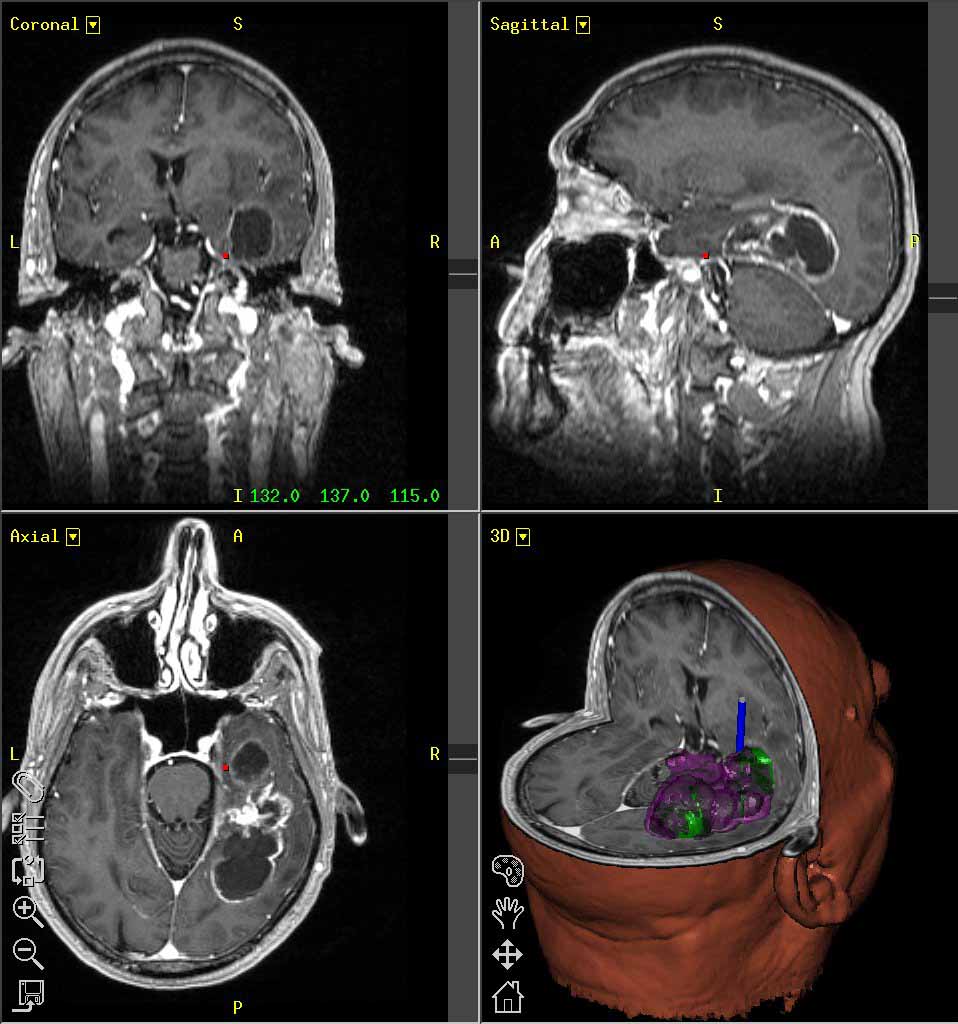

Glioblastoma Multiforme (GBM) – Subtype Analysis Lance Parsons Introduction Clinicians (meat readers) determine histological categorization: Astrocytoma, Oligodendrocytoma, Mixed, or Glioblastoma multiforme (GBM) GBM patients have poor prognosis, but some surive unexpectly long. ... Read Full Source